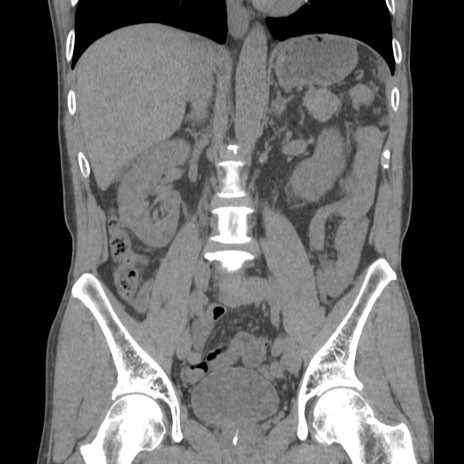

症例56 CT(冠状断像)

横断像